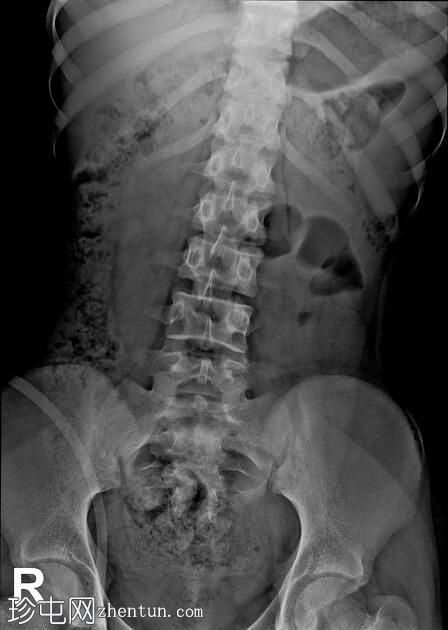

年龄:12岁

性别:女

透视检查

正位

排尿性膀胱尿道造影显示尿液反流至

肾脏

,伴有输尿管和肾盂肾盏系统轻度扩张。

还观察到排尿后残余尿。

本病例描述了一例有复发性尿路感染病史的儿童,其双侧3级膀胱输尿管反流。